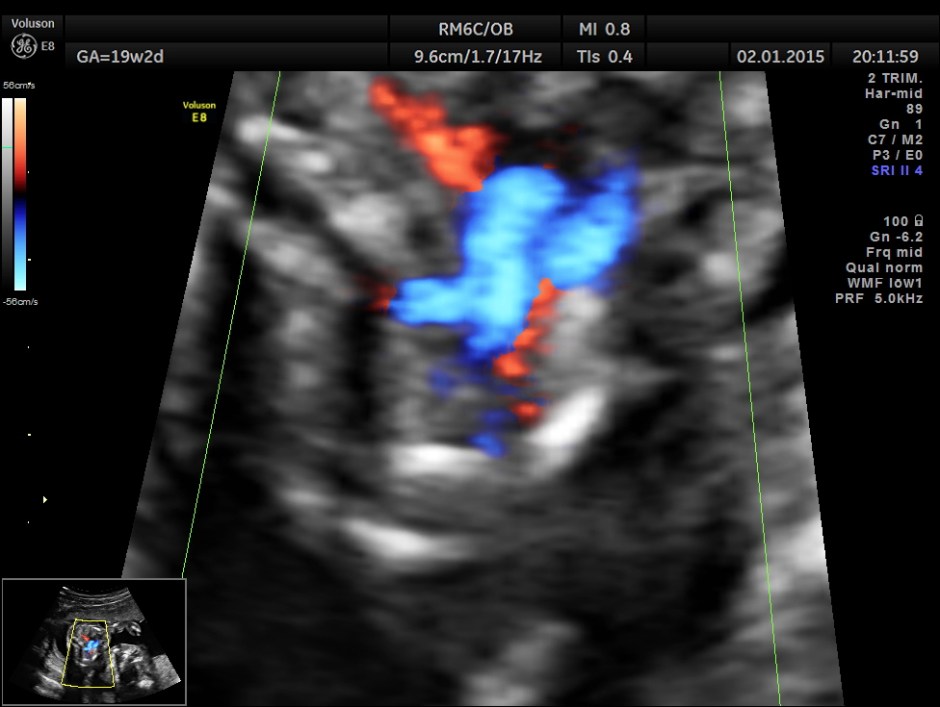

A prominent muscular ventricular septal defect is seen.

Great vessel crossing is seen.